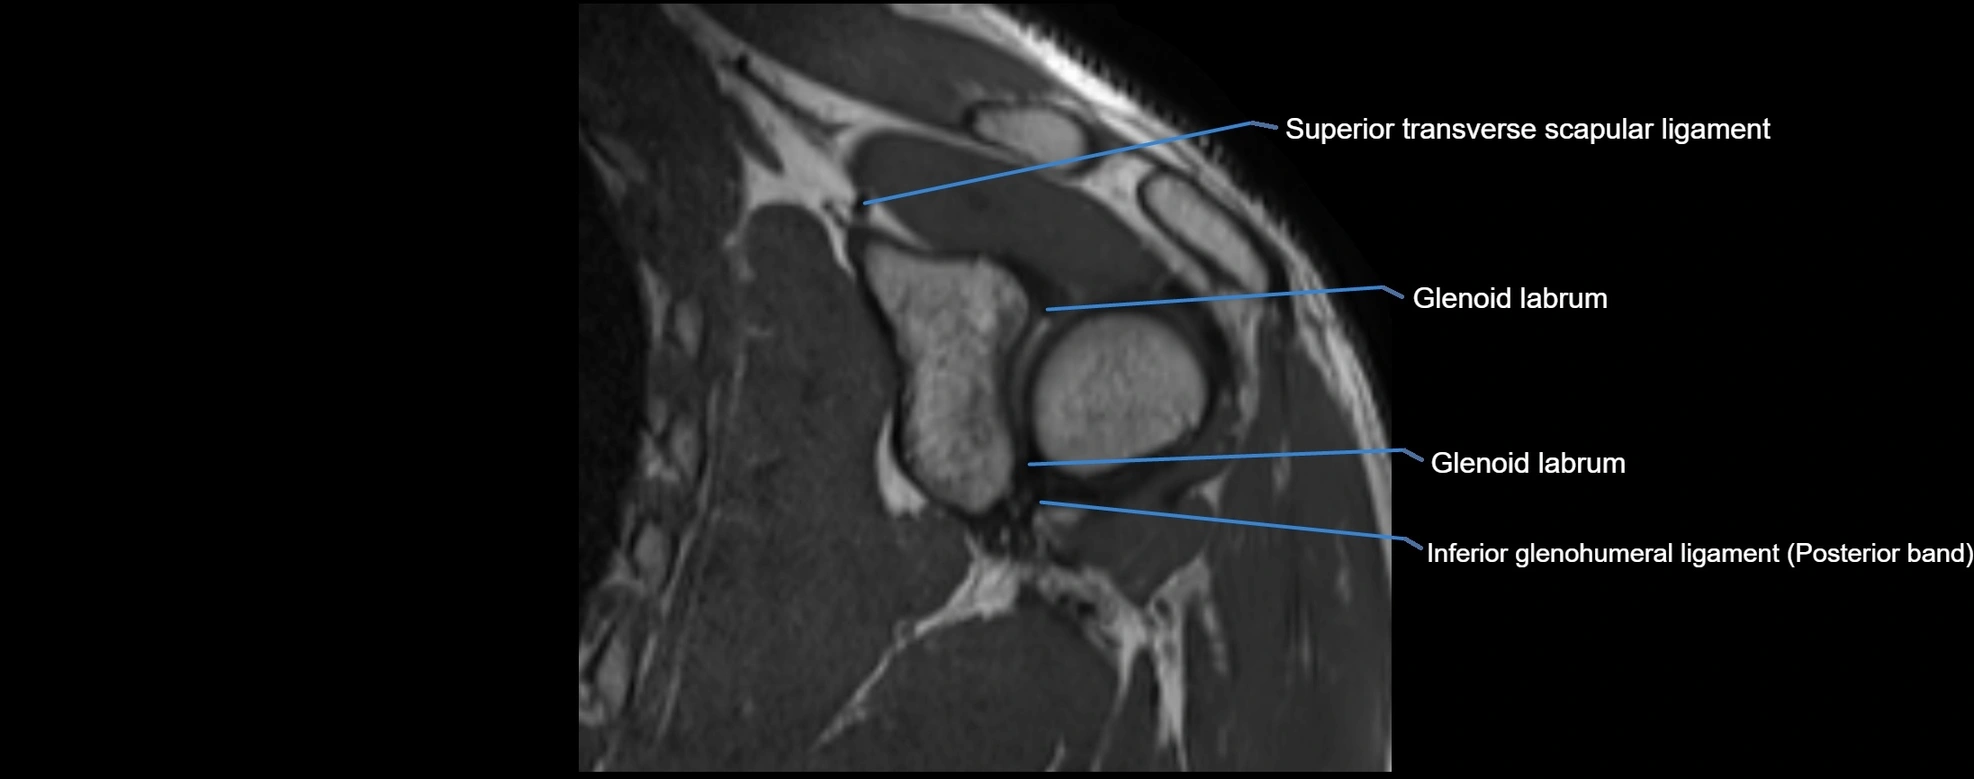

MRI images

image

MRI Appearance

• T1-weighted images:

• Normal ligament: Low signal (dark linear band) spanning acromion to clavicle.

• Surrounding fat planes: Bright, delineating the ligament clearly.

• Marrow of clavicle and acromion: Bright due to fatty content.

• Tears: Discontinuity or irregular thickening with intermediate-to-bright signal.

• Chronic injury: Thinning, fraying, or irregular low-signal fibers with adjacent scarring.

• T2-weighted images:

• Normal ligament: Low signal, homogeneous.

• Partial tear or sprain: Focal hyperintensity or thickening.

• Complete tear: Discontinuity with fluid-bright gap between clavicle and acromion.

• Associated edema: Bright signal in distal clavicle or acromion marrow.

• STIR:

• Normal ligament: Dark linear band.

• Injury or inflammation: Bright hyperintense signal in and around ligament fibers.

• Highlights periligamentous soft-tissue edema, especially in acute trauma.

• Proton Density Fat-Saturated (PD FS):

• Normal ligament: Low signal, uniform thickness.

• Partial tear or sprain: Bright signal or contour irregularity.

• Complete tear: Clear discontinuity with bright signal gap and joint effusion.

• Excellent for assessing joint capsule, coracoclavicular ligaments, and periarticular edema.